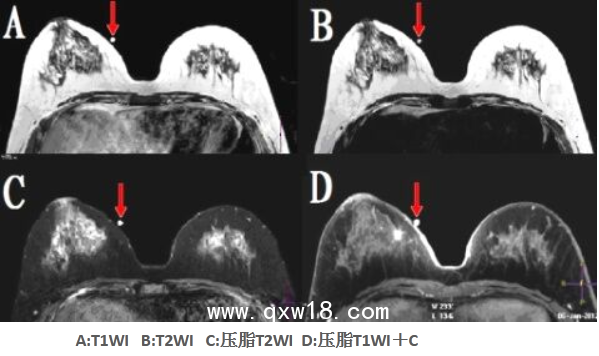

醫(yī)學(xué)圖像體外定位貼(MK⊙MR)產(chǎn)品說明:

?CT/MR導(dǎo)航型

該型號定位貼尤其適用于神經(jīng)系統(tǒng)定向穿刺活檢、機(jī)器人導(dǎo)航手術(shù)等,比國外同類產(chǎn)品優(yōu)點(diǎn)突出:①球和座可組可分;配準(zhǔn)注冊孔為陽性標(biāo)記。②座受壓不變形。③在CT、T1WI、T2WI、FLAIR(壓水像)、STIR(壓脂像)等多個掃描序列上均成像明顯。④經(jīng)在北京航空航天大學(xué)研制的立體定向神經(jīng)導(dǎo)航機(jī)器人上驗(yàn)證,標(biāo)記定位的精度高于國外產(chǎn)品。